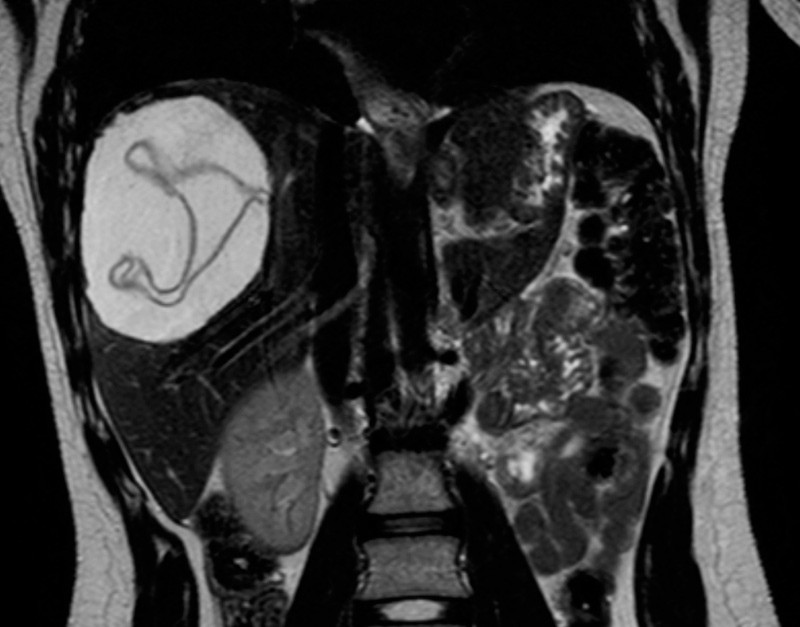

Tre år senere fikk hun magesmerter på nytt. MR-undersøkelse av leveren viste fortsatt en stor cyste i høyre leverlapp (bildet til venstre). Cysten var unilokulær med flere septa. Den ble nå kirurgisk behandlet med aspirasjon, instillasjon av hypertont saltvann og deretter ekstirpert in toto (bildet til høyre). Mikroskopi av cysteinnholdet viste Echinococcus spesies.